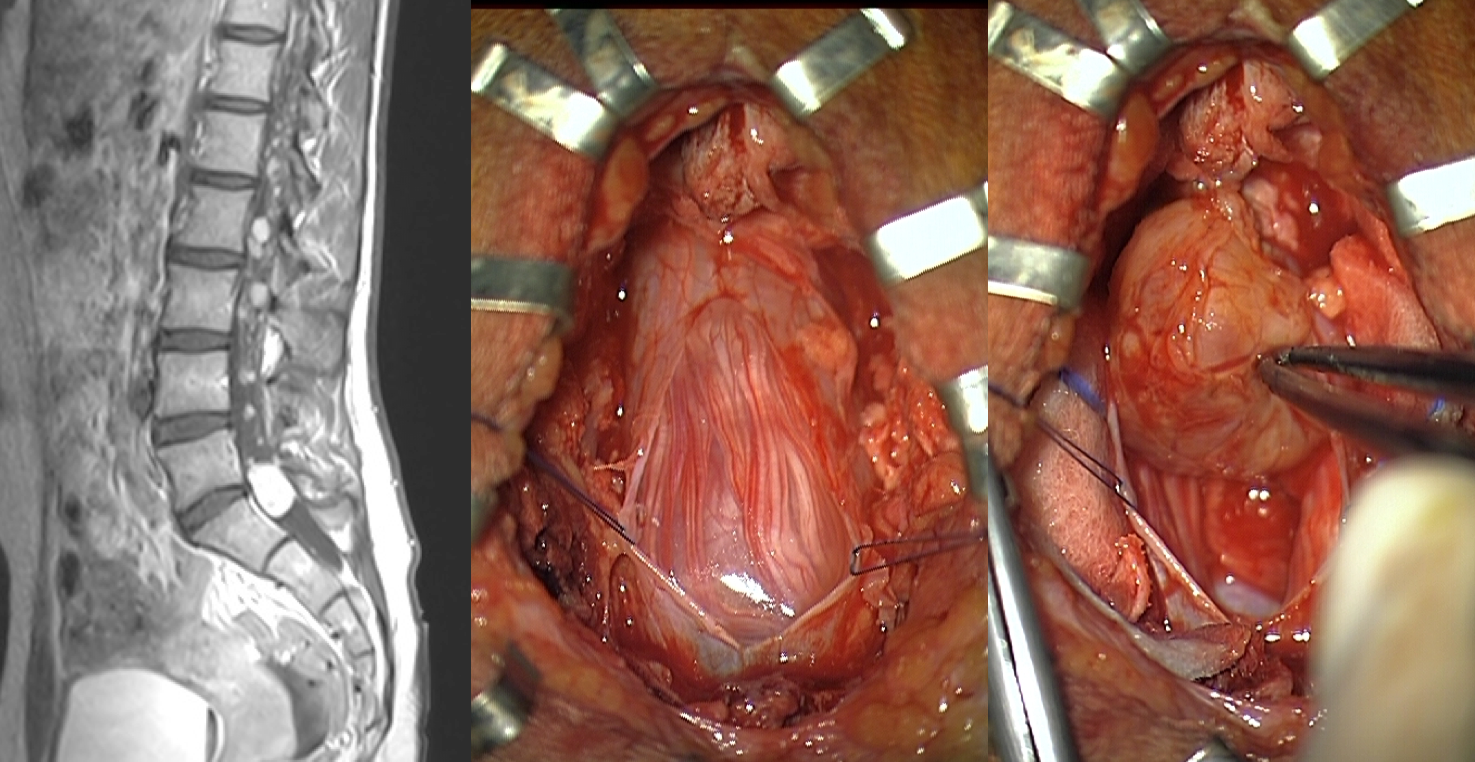

les hémangioblastomes

ce sont des tumeurs rares chez l’enfant, très vasculaires, souvent multiloculaires car dans le cadre d’un maladie de Von Hippel-Lindau ; le contrôle patient des pédicules artériels provenant des artèrioles radiculaires et des pôles rostral et caudal de la tumeur, puis de sa face antérieure permet de les dévasculariser progressivement et de les retirer de manière complète avec un bon résultat clinique (Cf. ci-dessous).